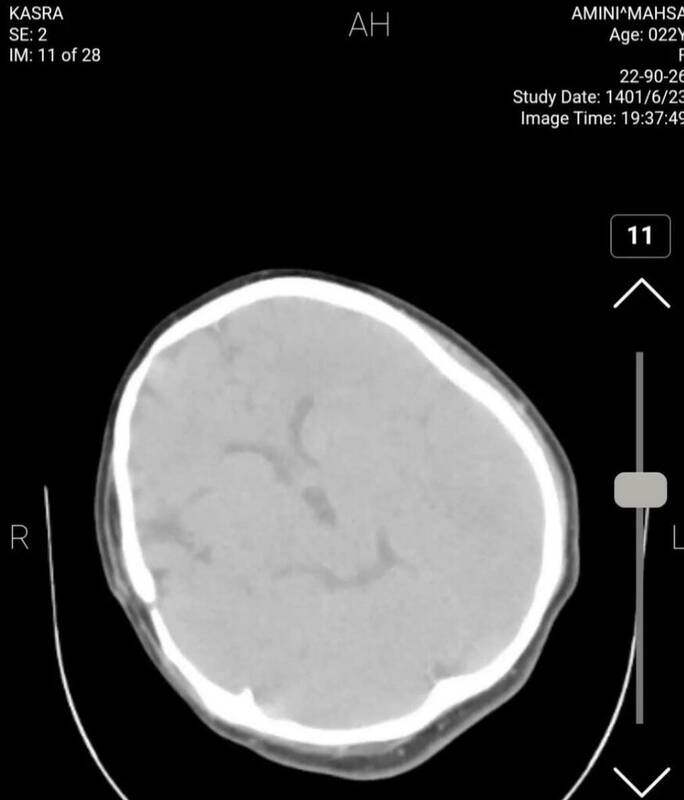

برای بررسی علمی این موضوع با تعدادی از پزشکان مغز و اعصاب و رادیولوژیست گفتوگو کردیم تا به صورت علمی این موضوع را بررسی کنیم. این متخصصان معتقدند بررسیهای سی تی اسکن بیمارستان نشان میدهد هیچ شواهدی از ضربه به سر و خونریزی در این تصاویر به چشم نمیخورد.

یک متخصص جراحی مغز و اعصاب گفت: بررسیها نشان میدهد که بیمار در گذشته جراحی در ناحیه سر انجام داده است اما براساس شواهد موجود از روی سیتیاسکن نمیتوان فهمید که جراحی دقیقاً مربوط به چند سال قبل است.

همچنین شواهد کرانیتومی فرونتوتمپورال قبلی همراه با آتروفی مختصر عضلانی و تغییرات بافت نرم در محل جراحی بیمار مشهود است.

یکی دیگر از پزشکان مغز و اعصاب نیز جراحی تومور بیمار را تایید میکند. به گفته این متخصص مغز و اعصاب متاسفانه برخی از افراد با دیدن تصاویر ناقص سی تی اسکن درفضای مجازی اقدام به اعلام نظر کردهاند اما واقعیت این است که در تصاویر کامل اثری از شکستگی نیست و این رسانه سعودی تصاویر را از زاویهای منتشر کرده است که شکستگی به نظر برسد.

برای بررسی دقیقتر موضوع سراغ پزشکی دیگری رفتیم. متخصص مغز و اعصاب دیگر میگوید: بیمار در گذشته جراحی سر انجام داده و بخشی از تومور در ناحیه سوپراسلار باقی مانده است. بررسی بیشتر سی تی اسکن بیانگر این است که با توجه به نوع جراحی انجام شده در این ناحیه وقوع دیابت بیمزه در بیمار دور از انتظار نیست و با توجه به آتروفی لوب فرونتال راست احتمال صرع را نمیتوان برای بیمار رد کرد هرچند اساساً تشخیص صرع یا دیابت بیمزه با سیتیاسکن مقدور نیست.